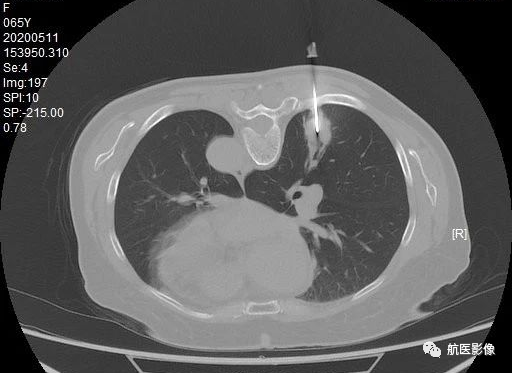

10. CT引导下肺活检:

利用CT定位引导肺穿刺抽吸或切针活检获取病理组织是一种微创、安全、准确的检查方法。 对于临床肺部病变的定性诊断、治疗方案的制定和预后的评估非常有用。 价值。